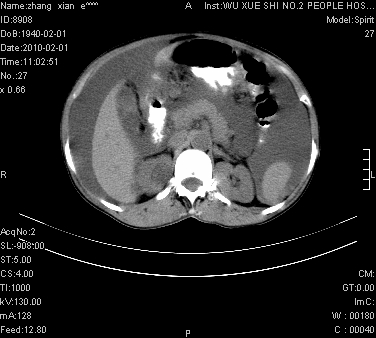

标题: CT24434:70岁 女 腹胀,腹水原因待查 [打印本页]

标题: CT24434:70岁 女 腹胀,腹水原因待查

大量腹水,脾脏囊性占位,子宫颈占位,右侧腹股沟淋巴结肿大,建议+c,先查妇科。

腹盆腔大量积液,子宫增大,子宫颈增大外形不规则,内见低密度影,膀胱后壁显示不清,右腹股沟肿大淋巴结,脾脏囊性占位,子宫颈占位,子宫颈癌?建议增强。

大量腹水,右肾、脾囊肿可能性大          考虑左侧附件区占位,建议增强